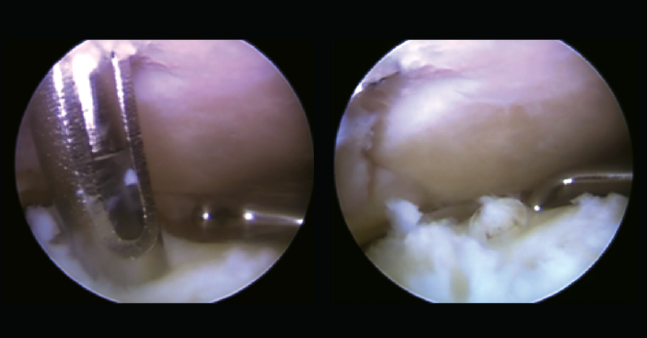

En un segundo tiempo se realizó un portal de trabajo mediante acceso transindesmótico anterior a 4 cm desde la línea tibioastragalina (Figura 3), previa disección roma en la piel, valorando la accesibilidad desde este punto de entrada a la lesión osteocondral previamente con una aguja de venopunción de 21 G × 1 1/2” (0,8 × 40 mm) y una vez localizado el punto de entrada con aguja de Kirschner de 1,5 mm de diámetro. Posteriormente, se realizaron nanoperforaciones en el hueso subcondral (Figura 4), reinserción del cartílago con implante reabsorbible de copolímero poliláctico (SmartNail®, ConMed Linvatec, Largo, FL) (Figura 5).

Figura 5. Reinserción mediante implante reabsorbible de copolímero poliláctico (SmartNail®, ConMed Linvatec, Largo, FL).

En un tercer tiempo se realizó abordaje posterior artroscópico, en decúbito prono, con portal posterolateral y posteromedial, hasta visualizar la articulación tibioastragalina, retirándose el cuerpo libre articular y observando una buena reinserción del fragmento osteocondral.